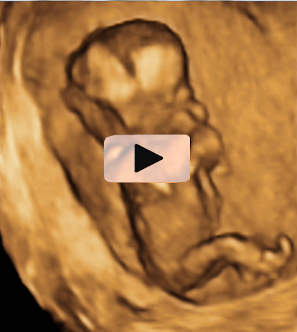

Ecografía 4D semana 12: Bebé con cordón umbilical al cuello

Ecografía en 3D de feto de 13 semanas con el cordón umbilical al cuello

La ecografía en tres dimensiones muestra un feto de 13 semanas de gestación con el cordón umbilical alrededor del cuello. En la imagen rotatoria se puede observar la situación del cordón, que sube por el tórax y que seguramente puede causar complicaciones en el embarazo.